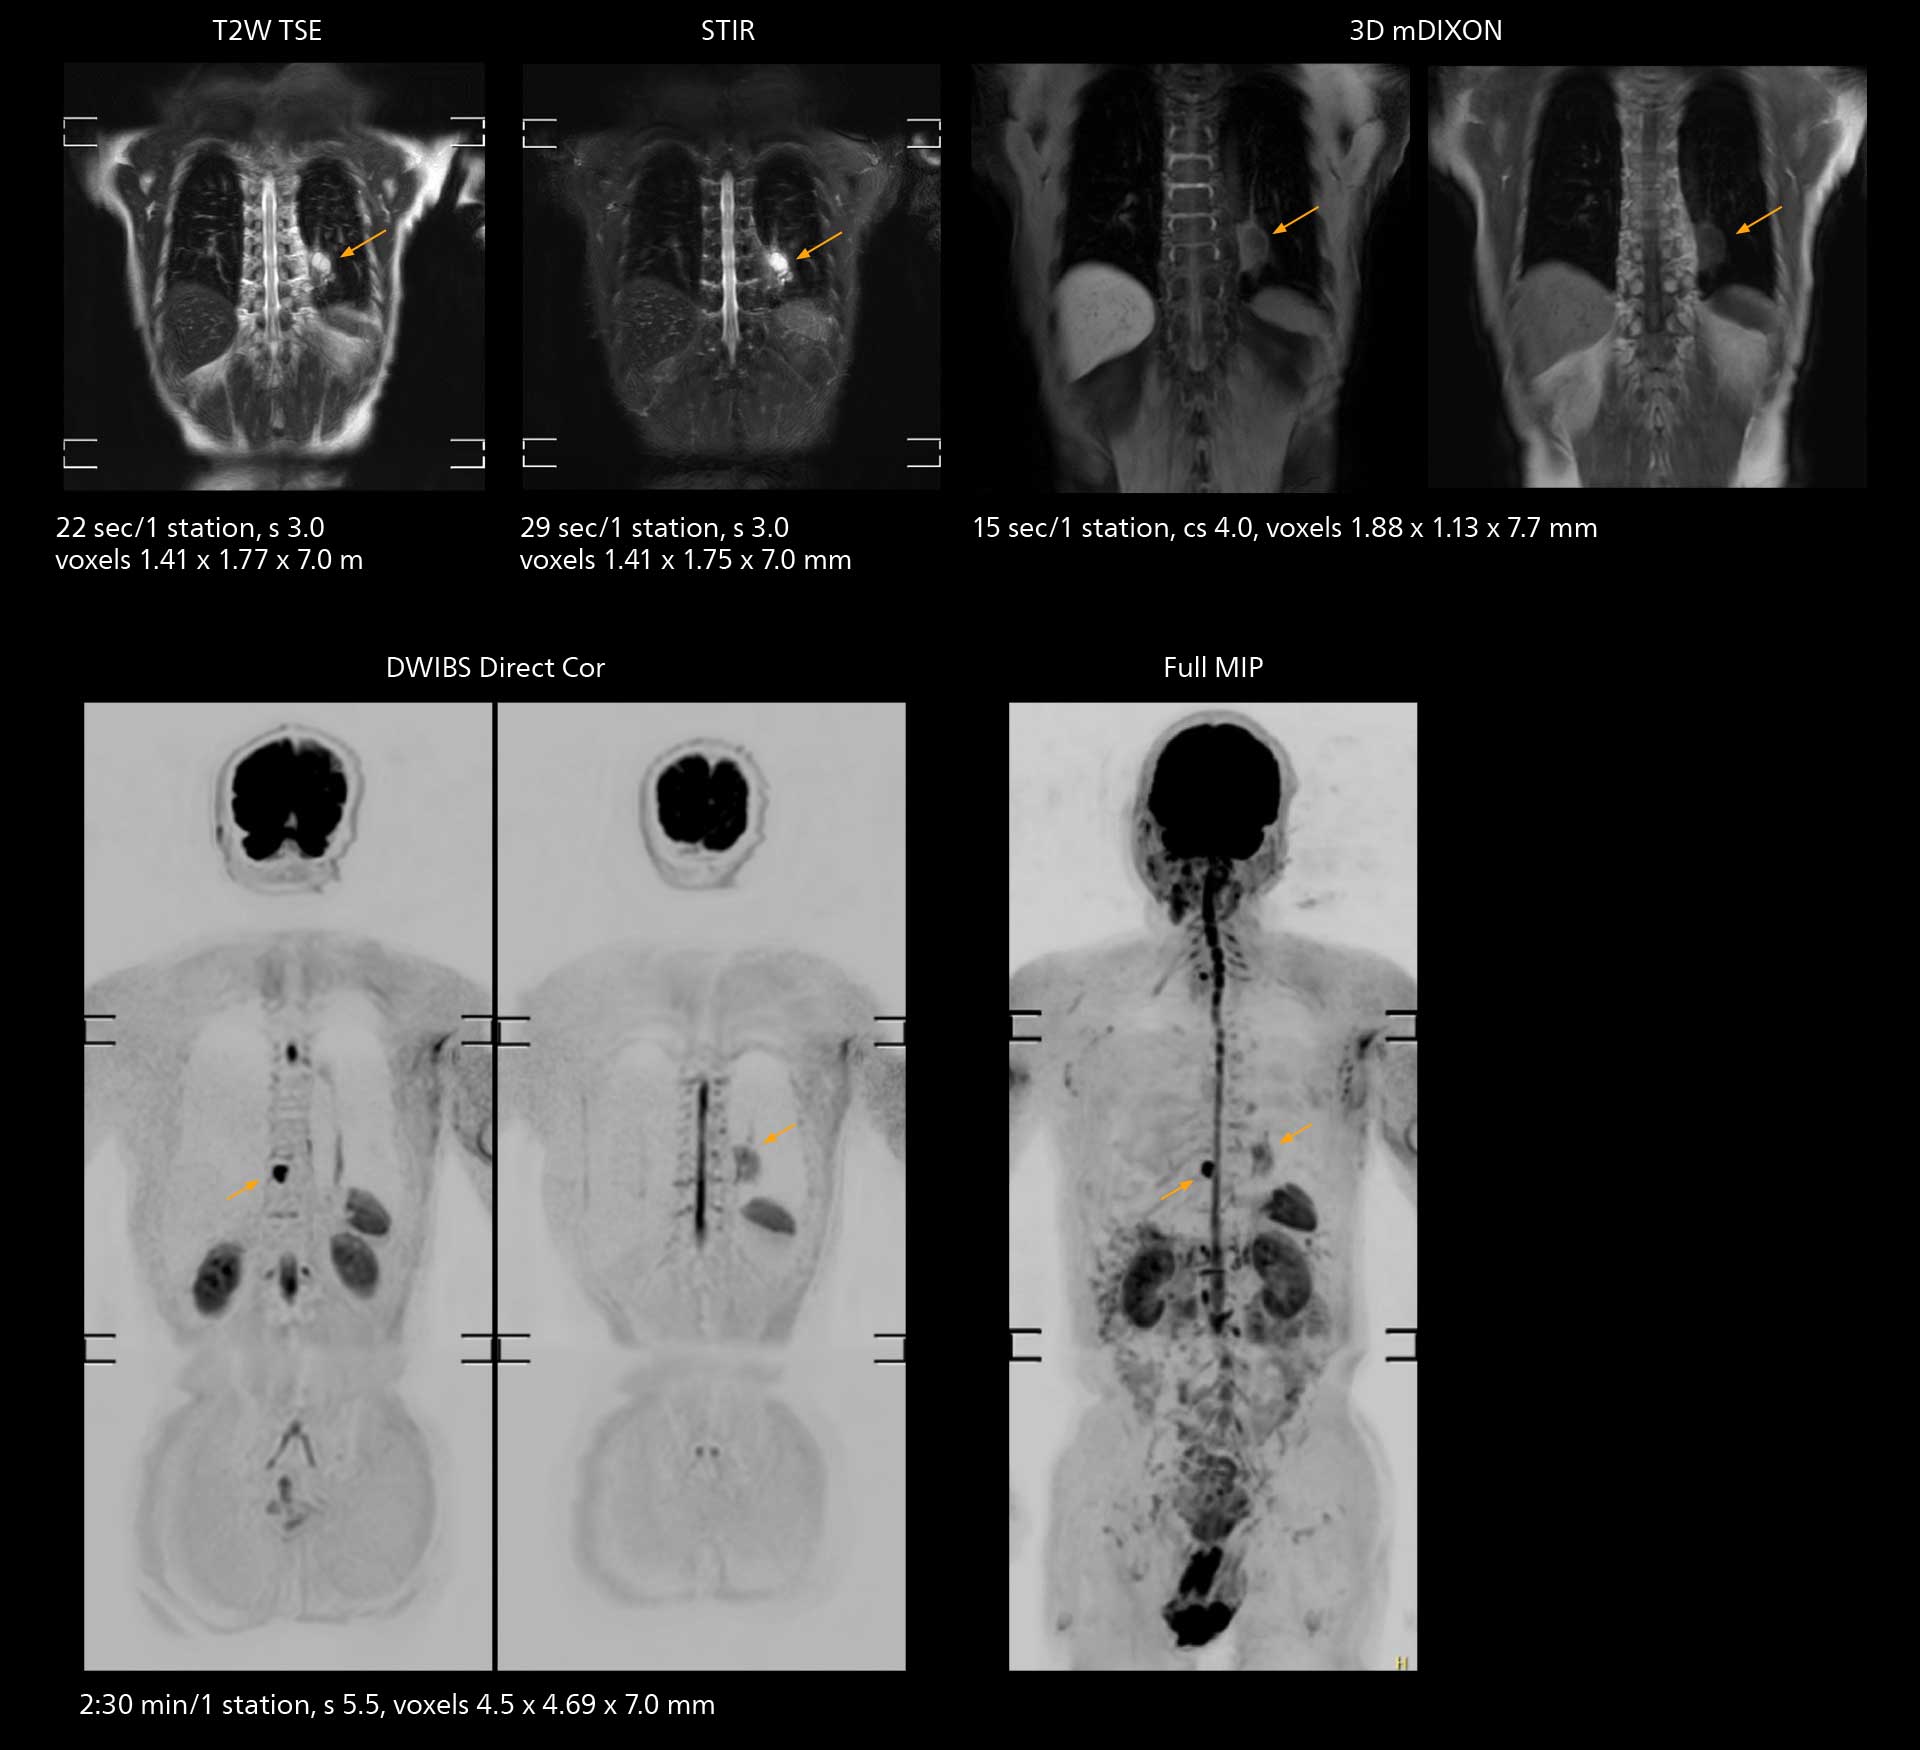

Fast whole body DWIBS examination

With SmartPath to Elition X the team can obtain excellent quality DWIBS imaging and reduce imaging time. Other sequences also fit in the examination slot. This case shows left paravertebral neurogenic tumor and Th10 vertebral hemangiomas.

Fast whole body DWIBS examination

With SmartPath to Elition X the team can obtain excellent quality DWIBS imaging and reduce imaging time. Other sequences also fit in the examination slot. This case shows left paravertebral neurogenic tumor and Th10 vertebral hemangiomas.